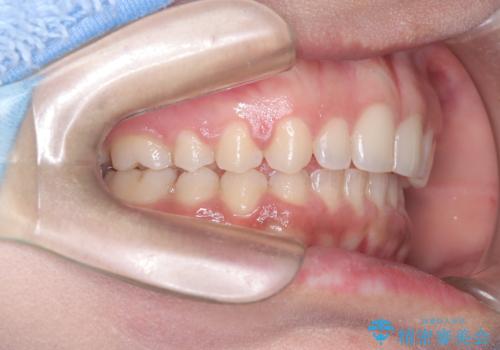

上顎前突を非抜歯で改善

- 患者様は、前歯が出ている状態(上顎前突)と隙間を閉じたいというご希望で来院されました。診断の結果、骨格性の上顎前突が確認されたため、理想的には外科矯正が必要であることを説明しましたが、患者様の「非抜歯でできる範囲で治療を進めたい」という希望を尊重し、矯正治療計画を立てました。治療目標は、前歯の突出を可能な限り改善し、隙間を閉じることに重点を置きました。

本症例では、非抜歯での治療を選択したため、スペースを確保するためにIPR(歯間削合)を行い、歯列を整えました。オーバージェット(上の前歯と下の前歯の水平的なズレ)は残る結果となりましたが、見た目や機能の改善を重視し、患者様と治療計画を共有しながら進めました。治療中は、歯列全体のバランスと噛み合わせを考慮しつつ、矯正装置の適切な使用を徹底しました。当初の計画通りに治療を完了し、患者様にも満足していただけました。